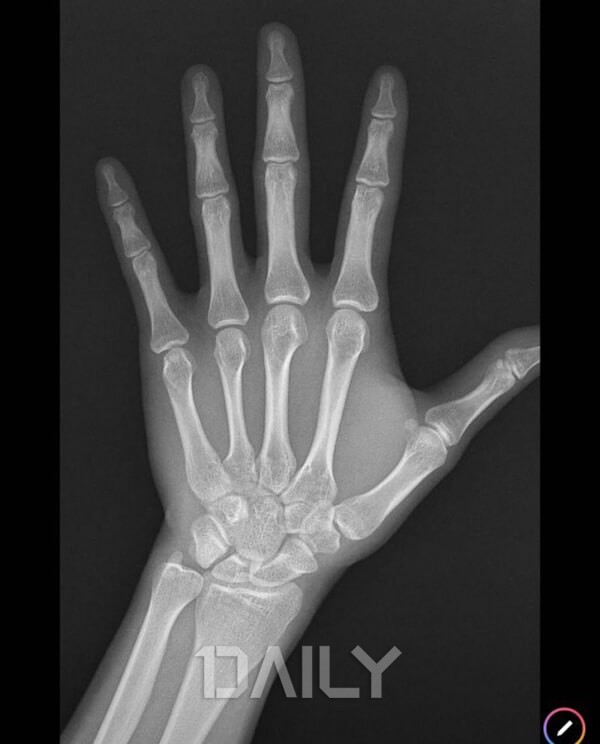

성장판이 닫히면 키가 안 클까?

성장판 세포는 점차 시간이 지나면서 딱딱한 뼈로 바뀌면서 활동이 줄어들게 되는데, 여자의 경우 약 15세, 남자의 경우 17세가 되면 성장이 멈춘다고 알려져 있습니다. 성장판이 닫히고 나서도 20세 전후까지 키가 자라기는 하지만 성장판이 닫히기 전과 비교했을 때 절반 정도로 성장 수치가 줄어들게 됩니다. 이 시기를 지나 성장판이 완전히 닫힌 후에는 뼈 성장이 더 이상 이루어지지 않습니다.